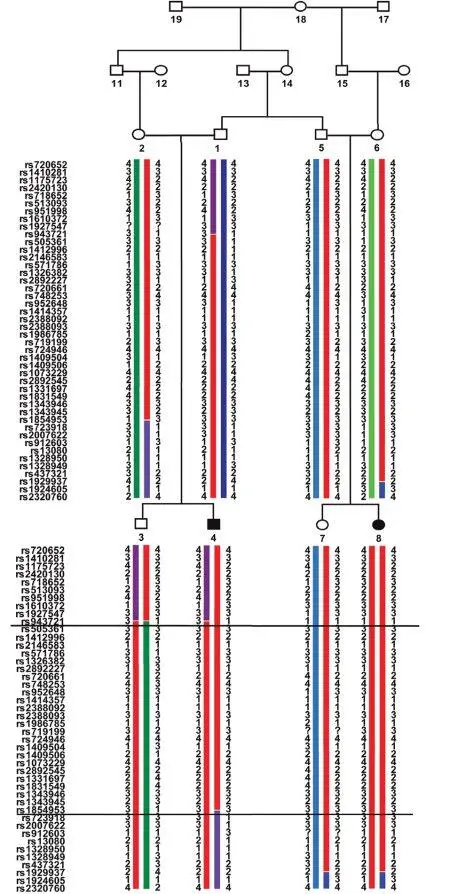

Рис. 19. Родословная и схема генов у больных с неонатальным сахарным диабетом

В 2010 году Nicolino М. et al. [160] провели генетическое исследование семьи, имевшей трех детей, больных неонатальным сахарным диабетом. В результате были выявлены новые мутации в гомеобоксных генах поджелудочной железы (PDX1, IPF1) (рис. 19).